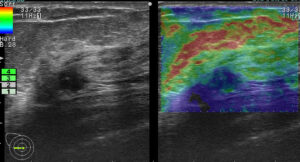

上に挙げた4つのエラストグラフィー

これが何を物語っているか?

エラストグラフィーは何か所見があった際に「これは怪しい!」と思わない限り追加で行わないものです。

これを実は4回も(昨年)行っていたのです。

つまり、(昨年も)その技師は「明らかに癌を疑っていた。」

この4枚のエラストグラフィーは技師の「これは怪しい所見です!是非要精査にしてください!」という心の叫びと言えるんだね!

まさに、その通り!

ただ、悲しいかな。技師さんのその「必死な思い」は、検診画像評価を行う医師には伝わらなかった。

結局、検診結果を出すのは(その画像を見て判断する)医師なのです!

正に診断の問題点1「画像評価」の過ちがここにありました。